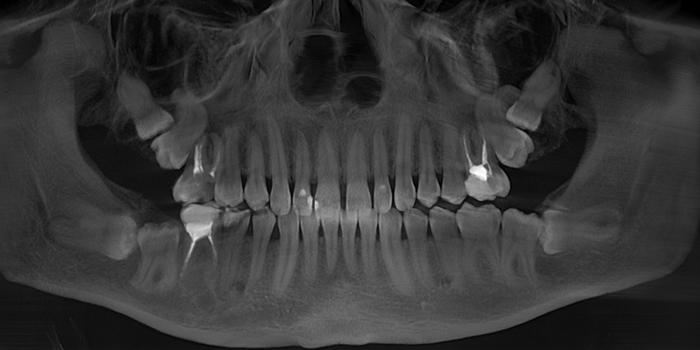

Время нещадно и неумолимо проносится, пациентка приходит в очередной раз на осмотр, ассистентка делает снимок и…

Добрый вечер… А что это значит?... Прекрасно видно, что фолликулярная киста начала расти и оттеснять зуб мудрости дальше в пазуху, что несколько затрудняет его удаление. Блять, подумал я, надо было сразу удалять.

Сделал глубокий вдох, тихонечко выдохнул и говорю пациентке, что этот день настал. Надо, дескать, зуб удалять, иначе пиздец. Девушка боевая, ее это не напугало. Она, кивнув головой, дала добро, и я приступил к операции.